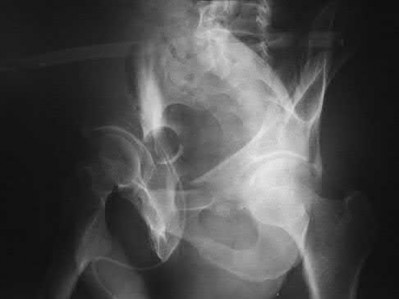

A 76-year-old male community ambulatory presented to clinic complaining of pain in the left groin that has been persistent for the last 8 months. Radiographs obtained from clinic are seen in Figure A. You suspect a femoral neck nonunion and obtain a CT scan which confirmed it. Which of the following statements is true?

A total hip arthroplasty (THA) after nonunion of a femoral neck fracture would provide the best long term outcomes in a 76-year-old male who is a community ambulator.

After nonunion of a femoral neck fracture, hemiarthroplasty and THA are good salvage option for the physiologically older patients. When deciding between these two options, THA is better for active and cognitively intact patients. THA is also indicated in patients with radiographic evidence of degenerative disease about the acetabulum. Hemiarthroplasty is advocated for patients who are older and less active.

Yang et al. retrospectively investigated the risk factors for nonunion in patients treated with cannulated screws. They reviewed 202 patients who had femoral neck fractures and were treated with internal fixation with cannulated screws. They identified that triangle configuration, displaced fracture, borderline or unacceptable reduction, and increased screw shaft subchondral purchase over the femoral neck were all risk factors for nonunion after internal fixation.

Inverted triangle configuration was found to increase rate of union.

Archibeck et al. retrospectively reviewed the outcomes of 102 THAs after failed internal fixation for a hip fracture (including both femoral neck and intertrochanteric). They concluded that the conversion of failed hip internal fixation has elevated risks compared to a primary THA, however, it may still be successful. The biggest concern for these patients postoperatively are periprosthetic fracture and dislocation.

Figures and Illustrations:

Figure A is an AP pelvic radiograph demonstrating a nonunion of a femoral neck fracture after suboptimal fixation with 3 cannulated screws in a triangle configuration.

Illustration A is an AP radiograph of the left hip in this patient following conversion to THA.

Illustration B is a radiograph demonstrating a valgus osteotomy. Illustration C shows an example of a femoral neck nonunion with varus malreduction.

Incorrect Answers:

Answer 2: Varus reduction is closely correlated with failure in this fixation method.

Answer 3: The patient's best outcome would be with THA.

Answer 4: This would be a good option in a younger patient, but given age and functional capacity, the best option is THA.

Answer 5: Patients with hemiarthroplasty have lower rates of dislocation.